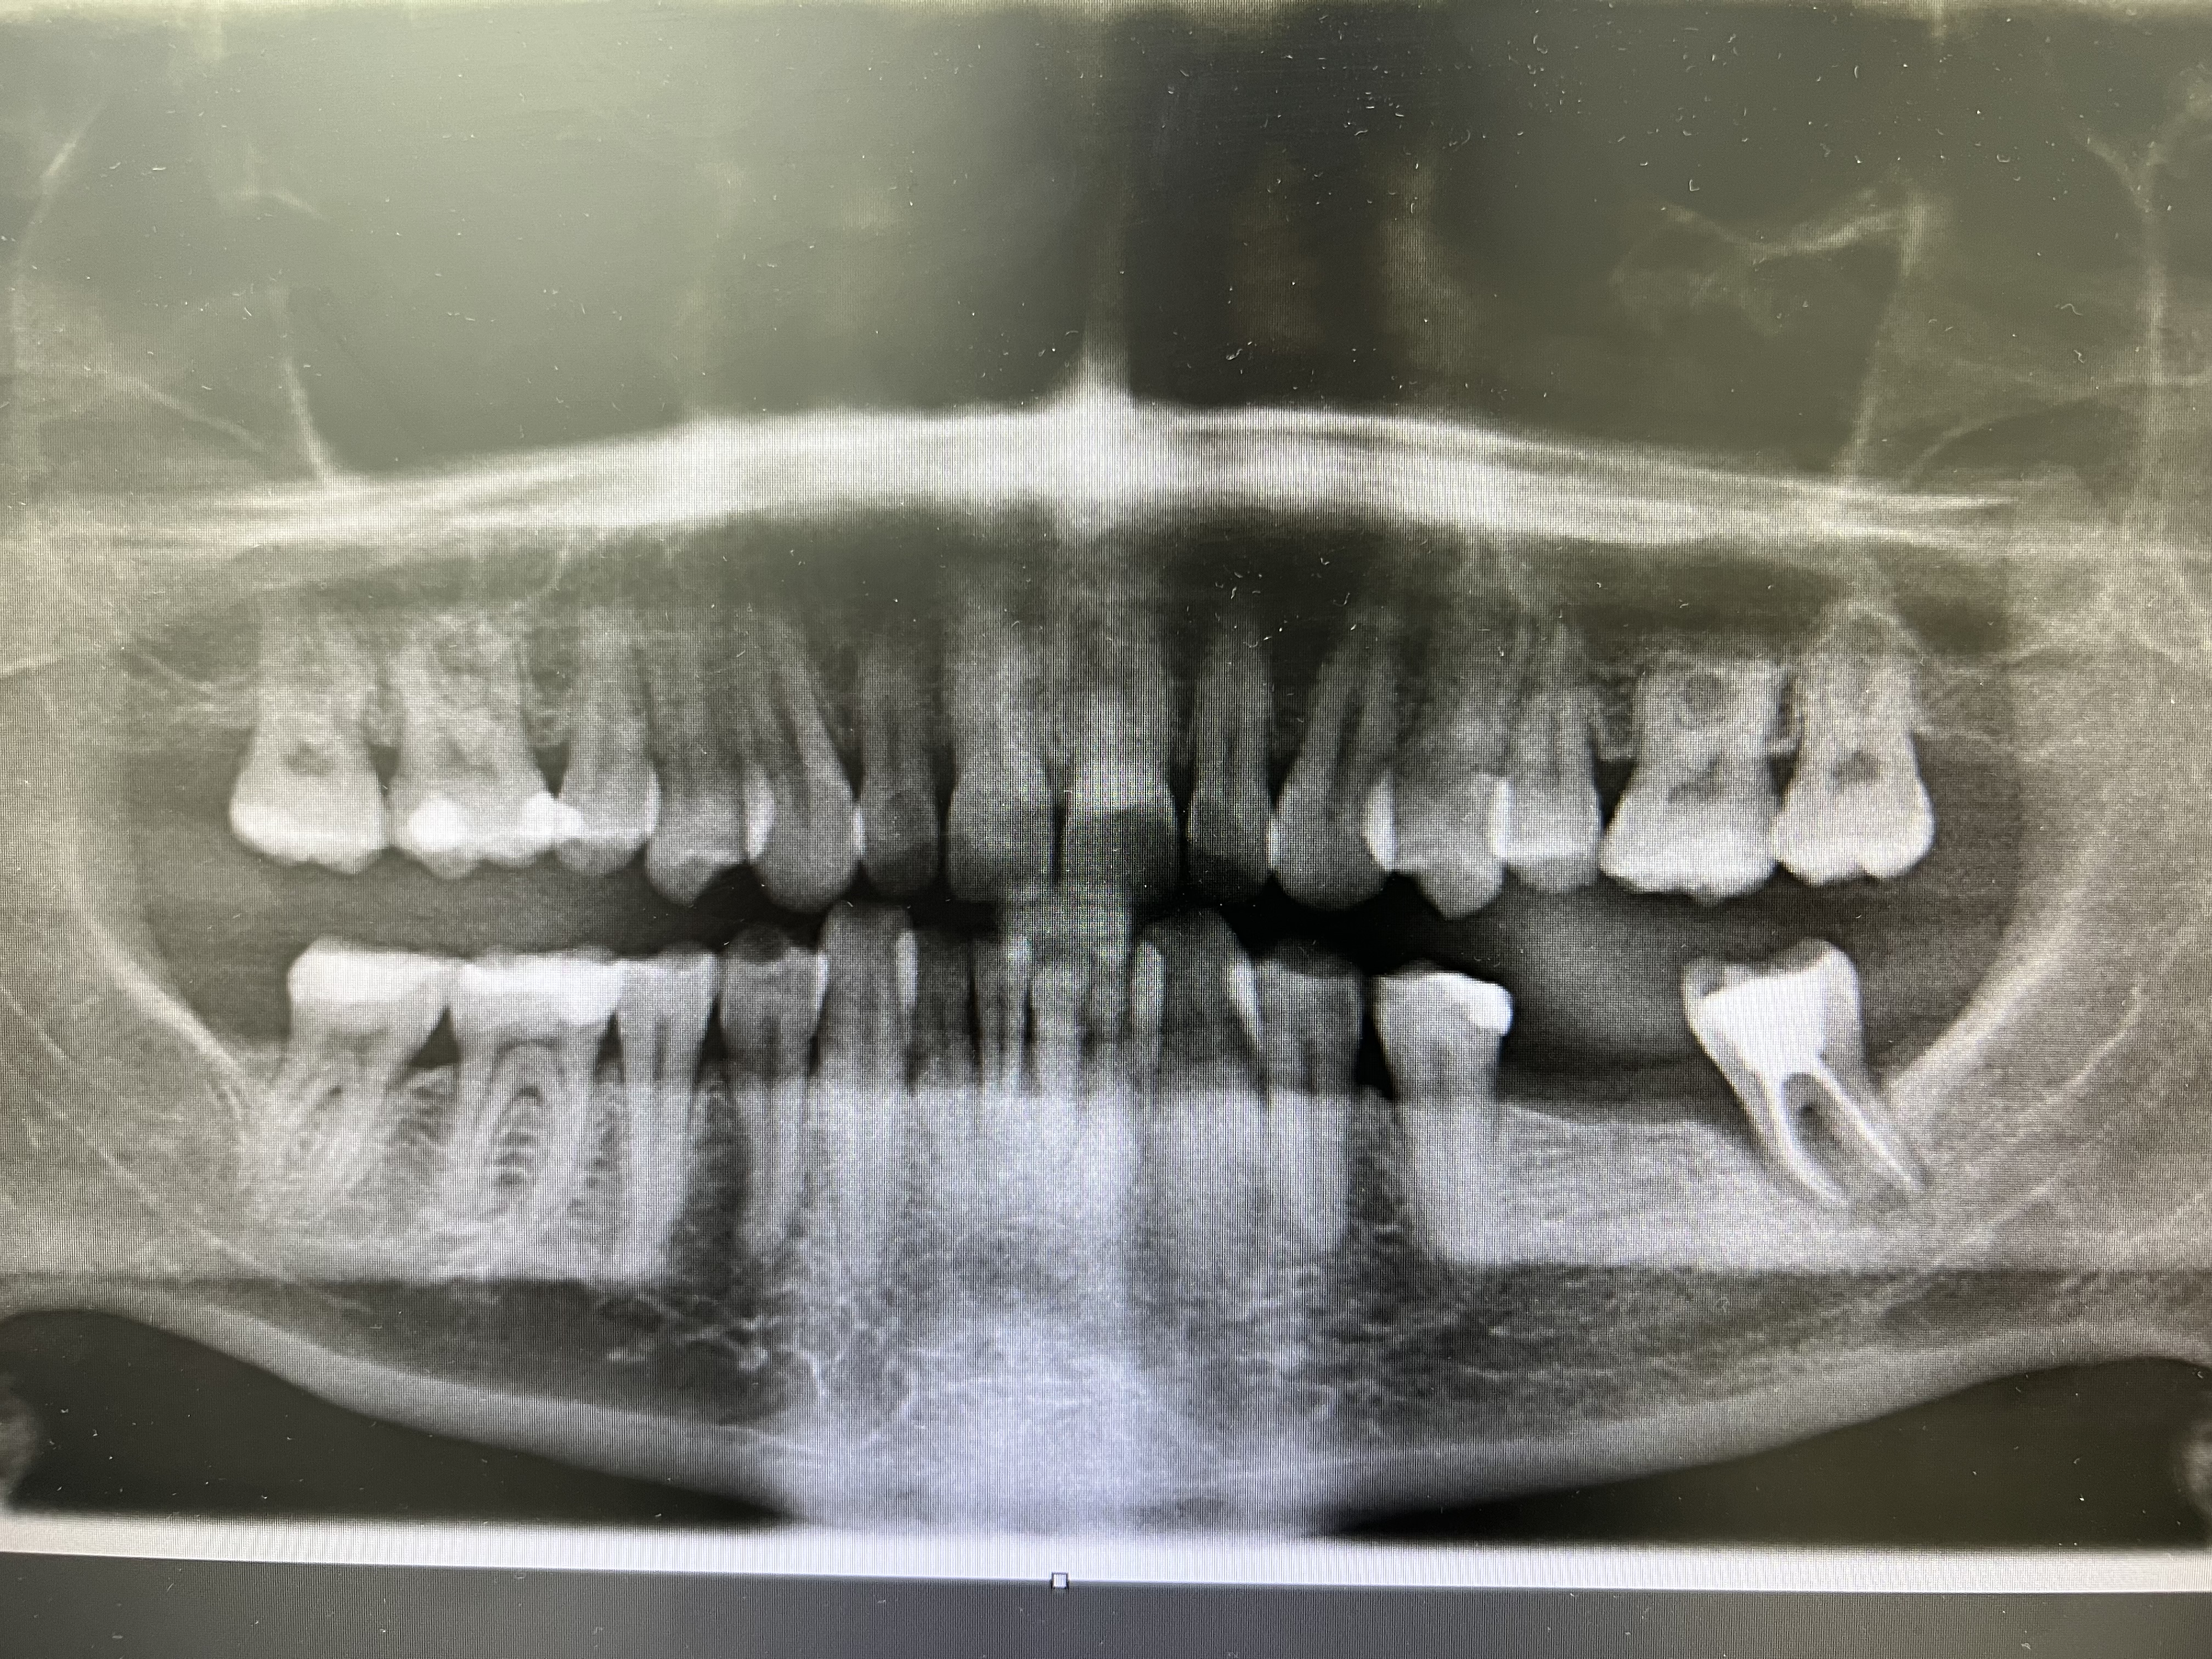

2 Implantate setzen mit Knochenaufbau und Kronen

I. Befund des gesamten Gebisses / Behandlungsplan

Oberkiefer

Unterkiefer

18 17 16 15 14 13 12 11

21 22 23 24 25 26 27 28

48 47 46 45 44 43 42 41

31 32 33 34 35 36 37 38